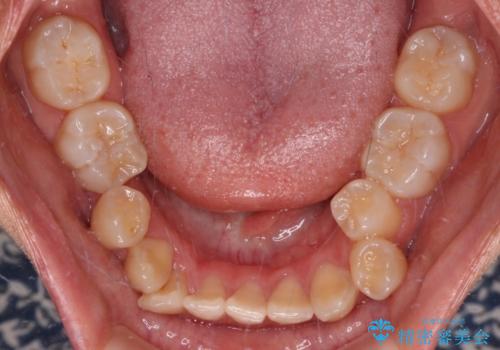

- 上下顎前歯部の非接触(開咬)と下顎のデコボコを主訴に来院された患者様です。

右側上下と左上の小臼歯が一本ずつ少なく、さらに骨格的な左右差もあり上下の真ん中の位置がずれています。

下顎のデコボコの解消と、真ん中の位置を改善するために左下の小臼歯を抜歯することとしました。